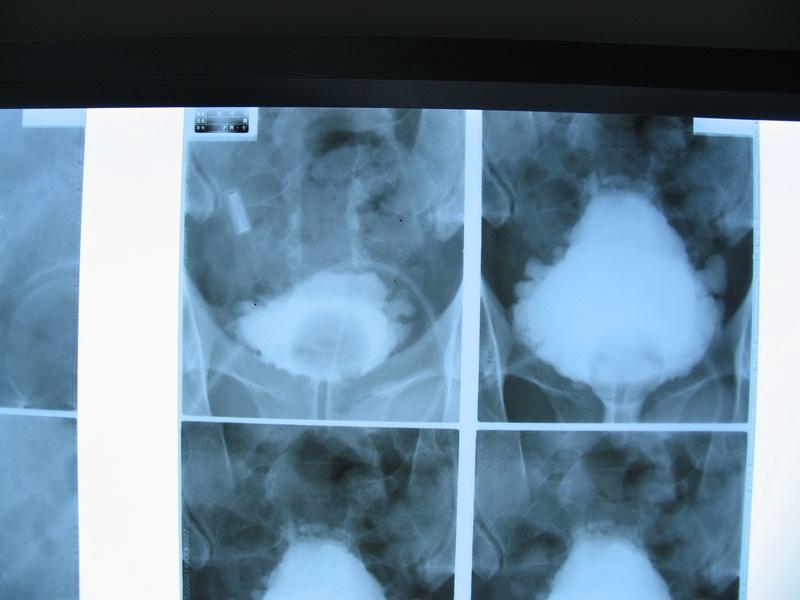

炎症性病变:正常的尿道,膀胱图:情形四:术后复查(如膀胱肿瘤电切术后

图片尺寸1280x960